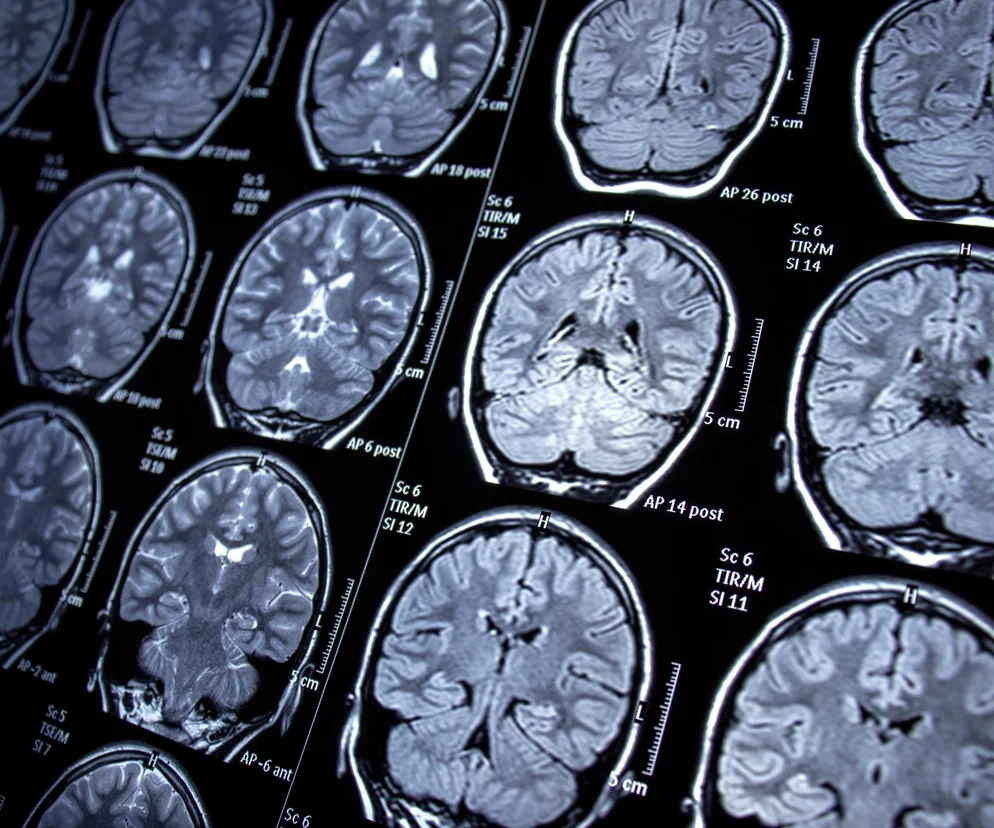

Epilepsja potoczne zwana padaczką to choroba, która ma prawie 70 odmian. Niemniej łączy je jedno, to neurologiczna przypadłość polegająca na zakłóceniu pracy neuronów w określonej części mózgu. Naukowcy na podstawie dużego badania klinicznego dostrzegli, że padaczka wiąże się m.in. z zaburzeniami poznawczymi, schizofrenią, czy chorobą Alzheimera.

Padaczka może uszkodzić mózg. Na liście 8 poważnych chorób

Autor: Getty Images

Badania opublikowane na łamach  Journal of Translational Medicine wskazują, że osoby chorujące na padaczkę mogą w wyniku tego schorzenia doświadczać wielu innych problemów natury neurologicznej lub psychicznej. Zauważono, że wśród uczestników badań chorych na padaczkę rozwinęła się nie tylko schizofrenia, ale i wiele innych zaburzeń.